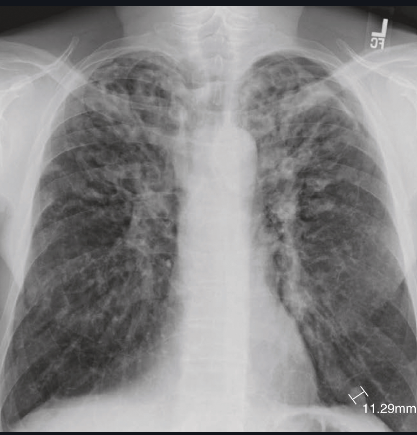

What can be seen on a CXR of bronchiectasis?

A

Tramlines - side one

Ring lesions - front on

Respresent dilated and thickened bronchial walls.